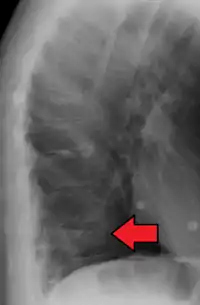

Compression fracture of T12

A compression fracture is a collapse of a vertebra. It may be due to trauma or due to a weakening of the vertebra (compare with burst fracture). This weakening is seen in patients with osteoporosis or osteogenesis imperfecta, lytic lesions from metastatic or primary tumors,[1] or infection.[2] In healthy patients, it is most often seen in individuals suffering extreme vertical shocks, such as ejecting from an ejection seat. Seen in lateral views in plain x-ray films, compression fractures of the spine characteristically appear as wedge deformities, with greater loss of height anteriorly than posteriorly and intact pedicles in the anteroposterior view.[3]

Compression fractures are usually diagnosed on spinal radiographs, where a wedge-shaped vertebra may be visible or there may be loss of height of the vertebra. In addition, bone density measurement may be performed to evaluate for osteoporosis. When a tumor is suspected as the underlying cause, or the fracture was caused by severe trauma, CT or MRI scans may be performed.